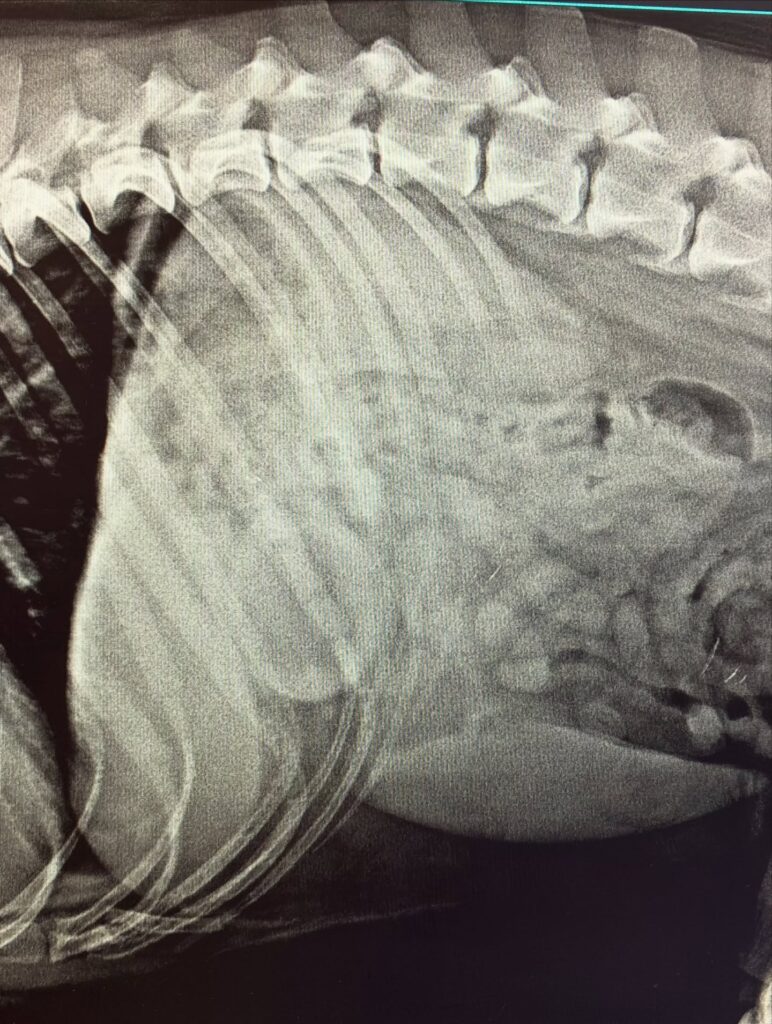

Arnošt se k nám dostal poté, co spolkl míček.

Nejprve jsme se pokusili o šetrné odstranění endoskopicky, bohužel to ale nebylo možné. Míček byl velmi kluzký a vzhledem k rozměrům se ho nepodařilo bezpečně zachytit a vytáhnout. (Viz video záznam z endoskopie)

Proto jsme museli přistoupit k chirurgickému řešení, při kterém se podařilo míček úspěšně odstranit.